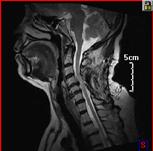

颈椎间盘突出、颈椎管狭窄——开展颈椎前路、后路手术治疗颈椎间盘突出、颈椎管狭窄,解除许多患者病痛,通过网上会诊方便患者,在家就能得到著名脊柱外科专家王少波教授诊治。

1).C4/5、C5/6间盘突出术前、 术后(C5椎体次全切除,钛笼植入)

2). C5-C6间盘突出术前、 术后(间盘切除,Cage植入)